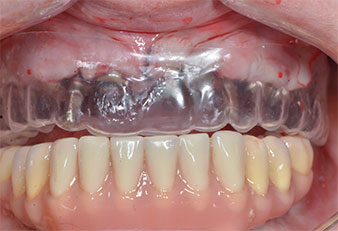

Una paciente de 41 años sin alteraciones sistémicas de interés perdió todos los dientes debido a la presencia de periodontitis y caries. Al final, esto le obligó a llevar prótesis completas mucosoportadas en ambos maxilares, lo que le ocasionaba grandes dificultades al masticar debido al deficiente ajuste de las mismas. Así pues, la paciente decidió someterse a la colocación de implantes para sujetar una prótesis CAD/CAM fija retenida por barra en el maxilar inferior.

Tres años después, llegó el momento de colocar una prótesis del mismo tipo en el maxilar superior. Basándose en una planificación mediante tomografía computarizada de haz cónico (CBCT, por sus siglas en inglés), se evitó la necesidad de realizar una elevación del seno utilizando implantes cortos, mientras que una plantilla quirúrgica sirvió para transferir las posiciones planificadas al borde alveolar (figuras 1 y 2).

Debido al hueso relativamente duro (D2) existente en el sector anterior, los sitios de los implantes largos de 10 mm de las posiciones 11 y 21 se finalizaron con una fresa rotatoria de 4 mm de diámetro, en combinación con un contra-ángulo quirúrgico WS-75 L de W&H, el motor de implantes Implantmed de W&H y el módulo opcional Osstell ISQ de W&H. En cambio, debido a la existencia de hueso blando, los sitios posteriores se prepararon hasta un diámetro final de 3 mm utilizando el inserto Piezomed I3P. Por último, los implantes se colocaron a nivel crestal para su osteointegración durante tres meses (figuras 6-10). La prótesis existente se mantuvo sobre cuatro implantes provisionales (figura 8).